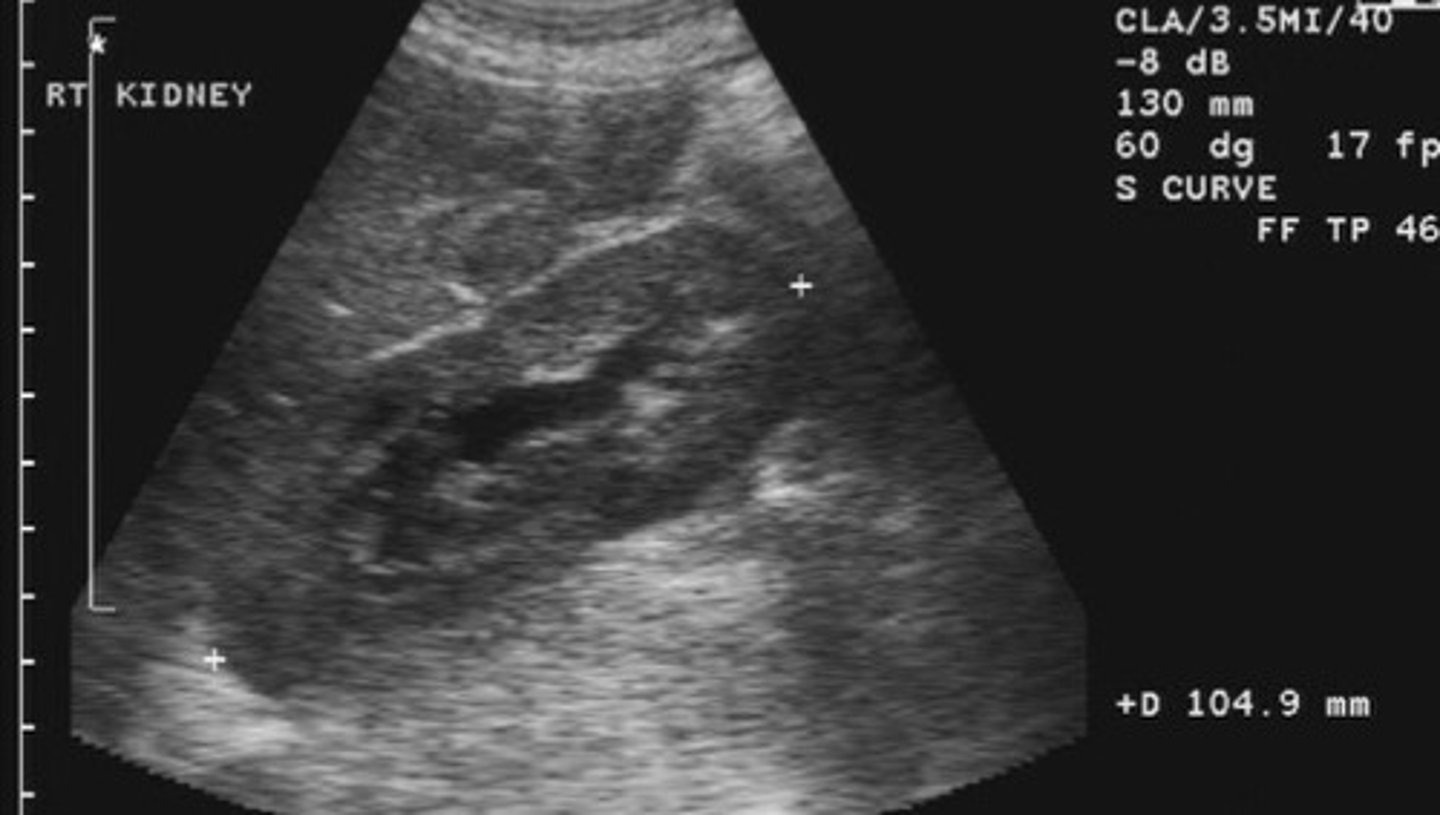

Nephrolithiasis

What does this image show